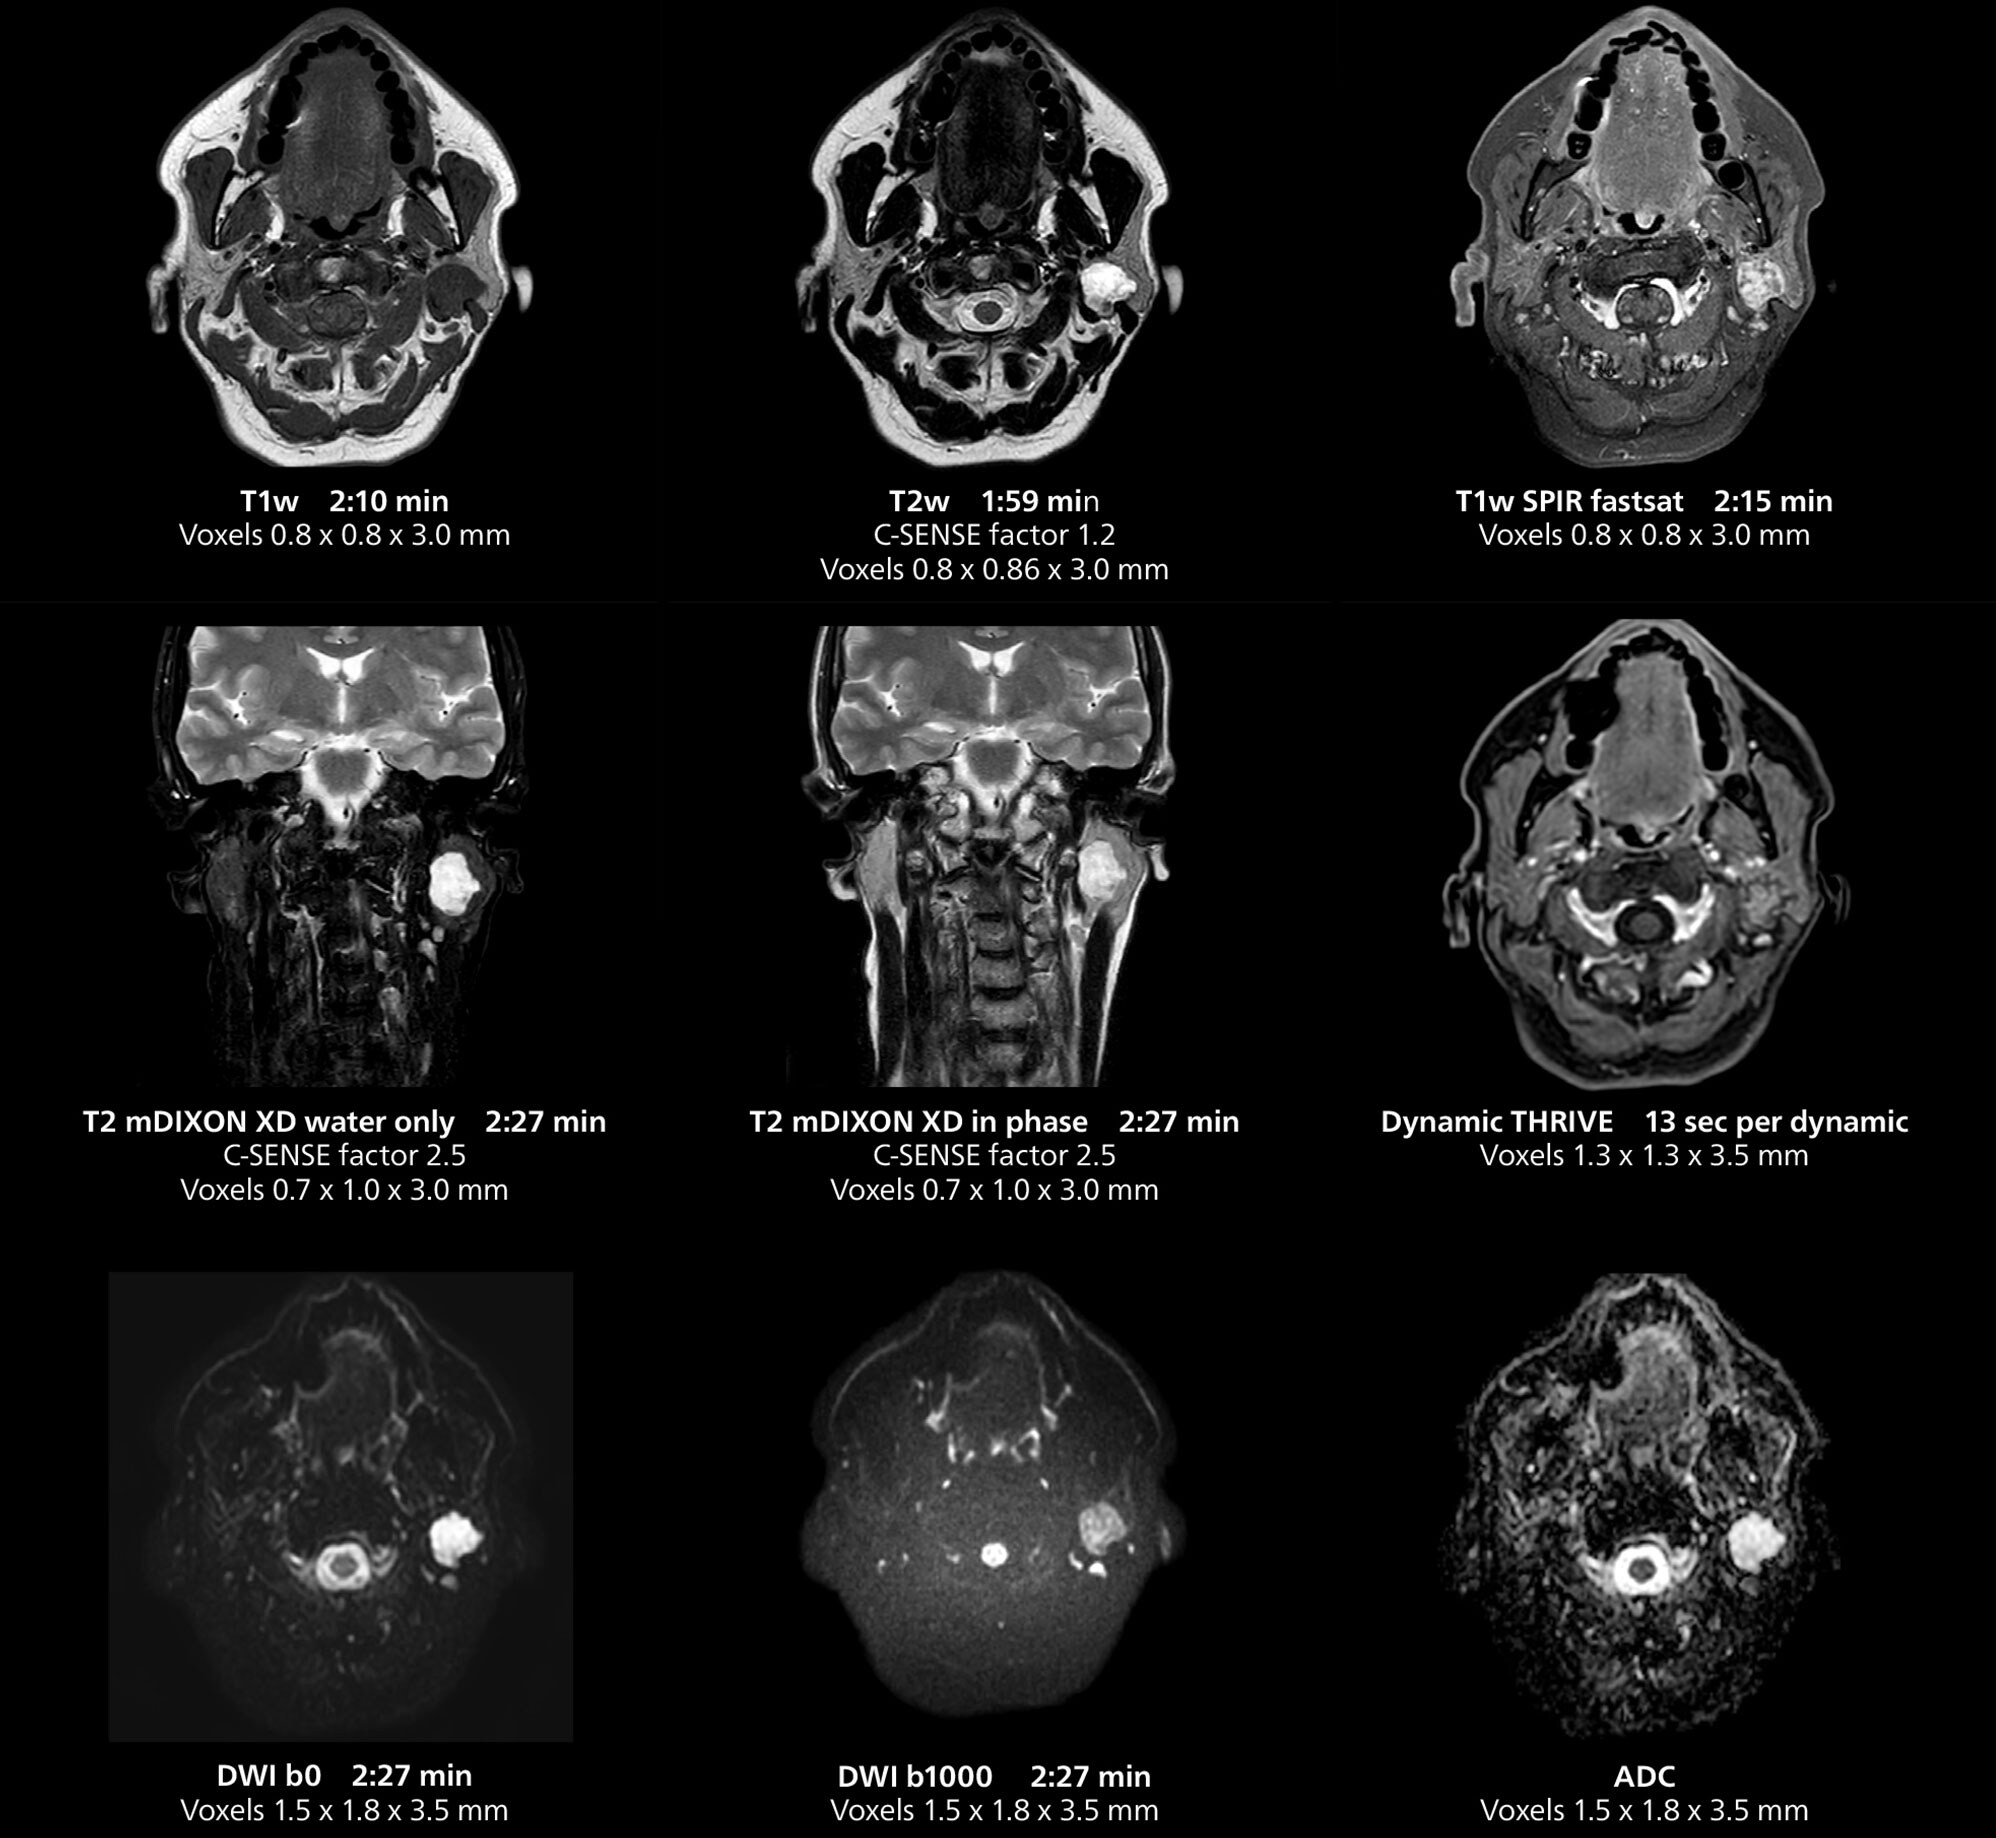

This MRI case illustrates imaging of salivary gland abnormalities with different sequences. Compressed SENSE allows to accelerate scanning while maintaining high quality. With mDIXON XD, different contrast types can be obtained from scanning one sequence.

The MR 5300 with Compressed SENSE is up to 50%** faster for many exams. It can provide routine exams in less than 5 minutes and whole-body exams in less than 20 minutes. Saint-Augustin has taken advantage of that speed to create highly efficient protocols. The hospital’s standard stroke protocol is just about 8 minutes, and standard ENT, prostate PIRADS staging, and endometriosis studies all clock in at just about 10 minutes.***

“We have more speed in 3D sequences,” Dr. Gellée states. “With Compressed SENSE, we can replace two or three 2D scans withone high-quality 3D scan. High quality additional orientations are then obtained by post-processing of the 3D data set, thus saving scanning time.”